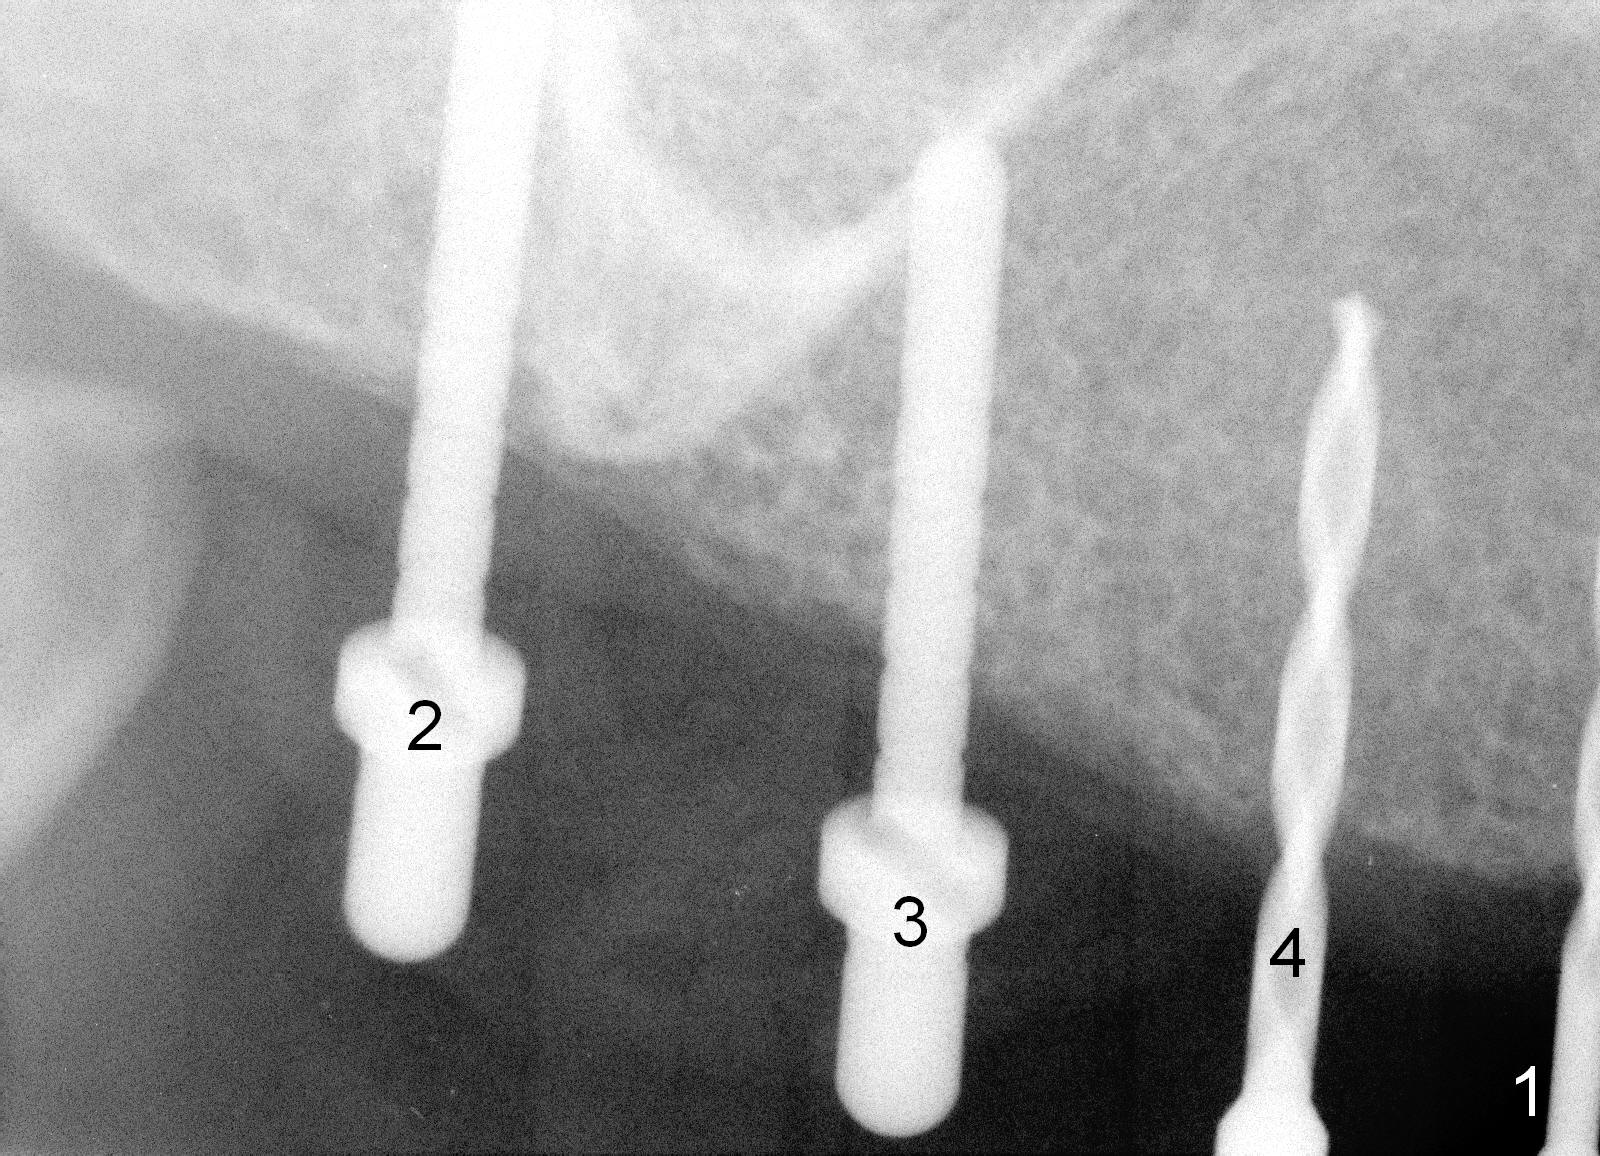

Osteotomy in the upper posteriors starts through a surgical stent for 12 mm. After incision, each osteotomy is examined, adjusted and extended 2 mm shy of intended (Fig.1,2). It appears that the trajectories at #4,5 are off (Fig.2). After re-adjustment, the trajectories are acceptable (Fig.3 (red dashed line; part of the root of the tooth #6)). Four implants are placed basically in accordance with the plan: 5.9x10 mm at #2, 5x14 at 3, and 3x14 mm 1-piece at 4 and 5 (Fig.4,5). Fig.6 shows the narrow ridge at #4 and 5 after implant placement. Although abutments are placed at #2 and 3, an immediate provisional bridge cannot be fabricated because of lack of enough clearance (supraeruption of the opposing dentition).